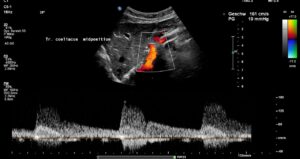

The systolic flow velocity in the abdominal aorta is only 80 cm/s. This indicates the compliance of the aortic vessel wall. However, in the celiac trunk, there are significantly increased flow velocities that vary with breathing, namely 161 cm/s in the middle respiratory position, 287 cm/s during inspiration, and 210 cm/s during expiration. This indicates ligamentum arcuatum syndrome, whose typical symptoms are vegetative symptoms such as nausea, circulatory dysregulation, disturbed peristalsis, sudden skin redness, and loss of appetite, as well as, of course, severe postprandial epigastric abdominal pain—the patient’s main symptom.

The arcuate ligament pushes the celiac trunk so far caudally that it leads to secondary compression of the superior mesenteric artery.

As a result of the compression, turbulent, highly accelerated flows are found in the vessel outlet, with 240 cm/s in the middle respiratory position, 226 cm/s during inspiration, and 196 cm/s during expiration.

Since both upper abdominal arteries are compressed, there is a risk of intestinal ischemia.